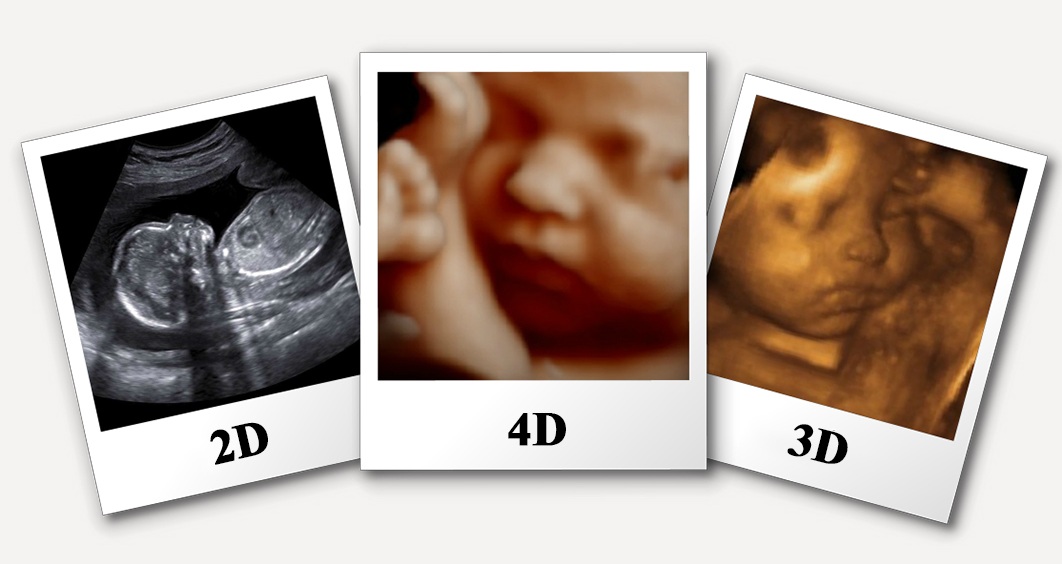

Arth Diagnostic provides a full suite of sonography in Udaipur, including 2D, 3D, and 4D imaging. These modern imaging techniques give precise insights into the structures and activities of the body, assisting in the correct diagnosis and monitoring of a variety of medical disorders. Arth Diagnostic’s experienced staff is devoted to providing high-quality and informative sonography services to fulfill your healthcare needs, whether you require a normal ultrasound or the extra dimension of 3D and 4D imaging for a more thorough look.

Certainly! As part of their extensive sonography services, Arth Sonography Lab in Udaipur offers both 3D and 4D ultrasound scans. These sophisticated imaging techniques provide extra dimensions and features, improving diagnostic capabilities and offering a more thorough image of the structures under consideration.

Arth Diagnostics is distinguished from other sonography clinics in Udaipur by its dedication to modern technology, extensive services, and patient-centered approach. They provide a wide range of modern ultrasound services, such as 2D, 3D, and 4D imaging, which provides thorough insights for exact diagnosis. Furthermore, Arth Diagnostics specializes in delivering digital reports, ensuring ease of access. Arth Diagnostics is a great choice for sonography in Udaipur because of their flexibility in fitting patient schedules and their skilled team’s devotion to excellent treatment.